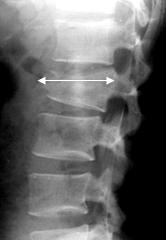

Признаком взрывных переломов, выявляемых при обзорной рентгенографии, является увеличение интерпедикулярного расстояния на прямой рентгенограмме (рис. 2А), увеличение переднезаднего размера тела позвонка - на боковой (рис. 2Б) и локальная кифотическая деформация в зоне перелома.

|

| А |

Б |

| Рис. 2. Рентгенологические признаки взрывного перелома тела позвонка |